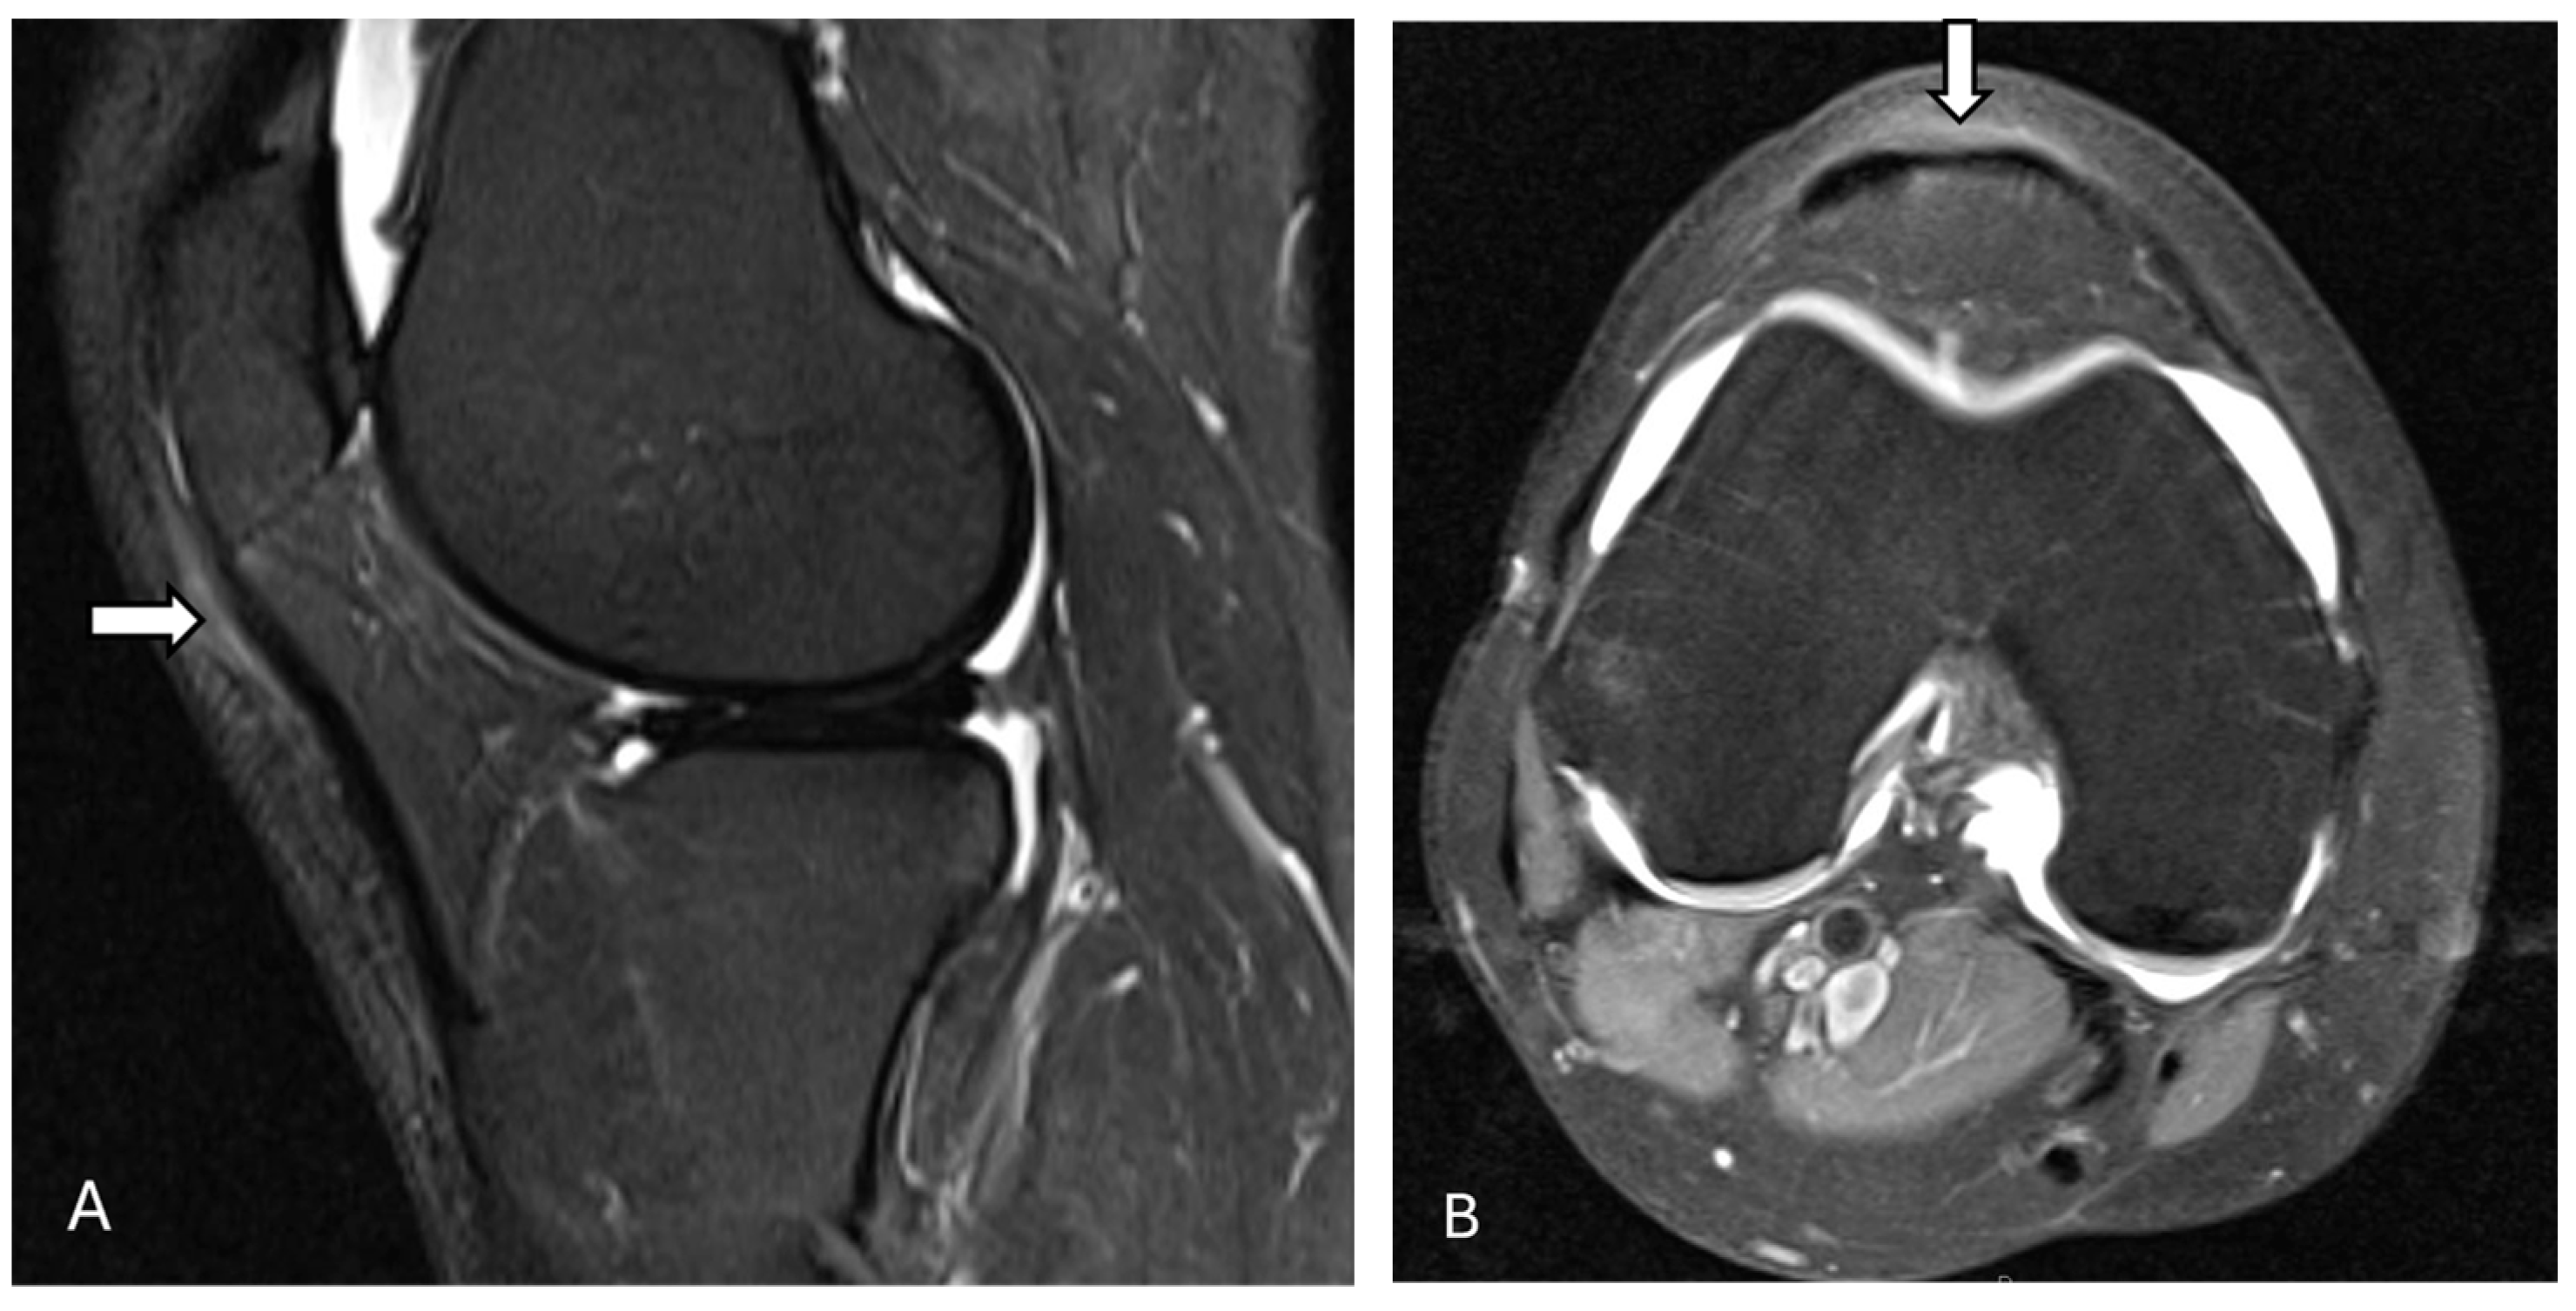

3.1. Acute Patellar Subluxation and Dislocation